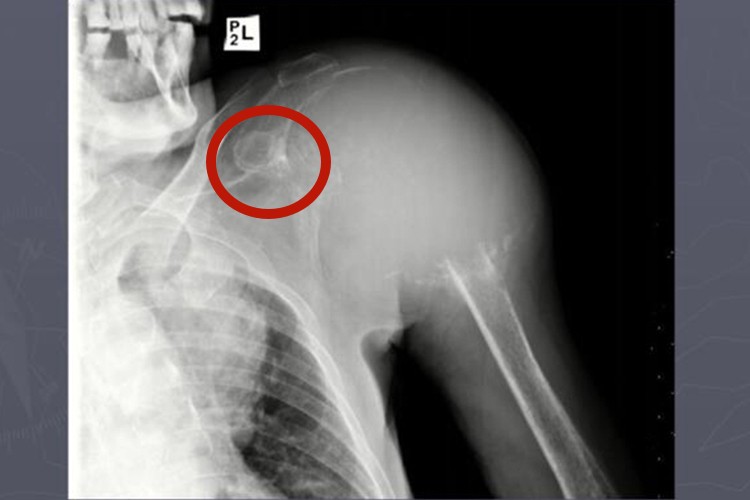

肩膀部位长骨肉瘤最常见的症状是短时期内出现疼痛和肿胀,肿瘤表面的皮肤可因肿瘤膨胀而紧绷,并且可见明显的浅表静脉充盈。X线检查可见长骨干骺端偏一侧有局限或广泛溶骨或成骨或两者相混的阴影,形状不一,边界模糊不清,骨皮质破坏,不膨胀被穿破。